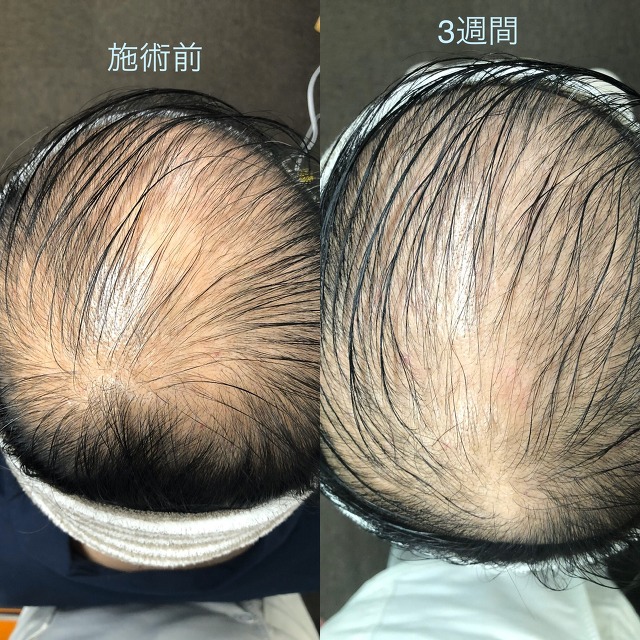

★発毛・薄毛部門からのお知らせ★

⚡薄毛・育毛にお困りの方に朗報です⚡

☑市販の育毛剤じゃ効果が出ない

☑抜け毛が気になってきた

☑全体的に髪のボリュームがなくなってきた

☑親族に薄毛の方がいる

こんな方はぜひご相談ください!

確実に満足のいく結果を出します!

嬉しいお知らせ!初回のカウンセリングは無料です。

完全予約制なので貸切でご相談いただけますので内容を聞かれる心配もなし!

あなたにとって「人生最後の発毛治療」にしましょう。

本気で私もあなたと向き合います!

「発毛のカウンセリングをお願い!」とご連絡下さい。

発毛専用ページ⇒https://peraichi.com/landing_pages/view/boubou1991

※「臍帯幹細胞の薄毛治療カウンセリングを受けたい」

とご連絡ください!

当院の発毛治療はオンラインでも対応しております。